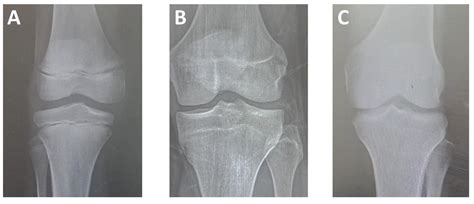

When the radiologist analyzes the Bone Age X-ray, they are looking specifically at the epiphyseal plates, often called growth plates. These are the areas of cartilage at the ends of the long bones. As a child approaches the end of their growth spurt, these plates harden and fuse together. Once they are fully fused, bone growth stops. The following table summarizes how skeletal age comparisons are typically interpreted by physicians.